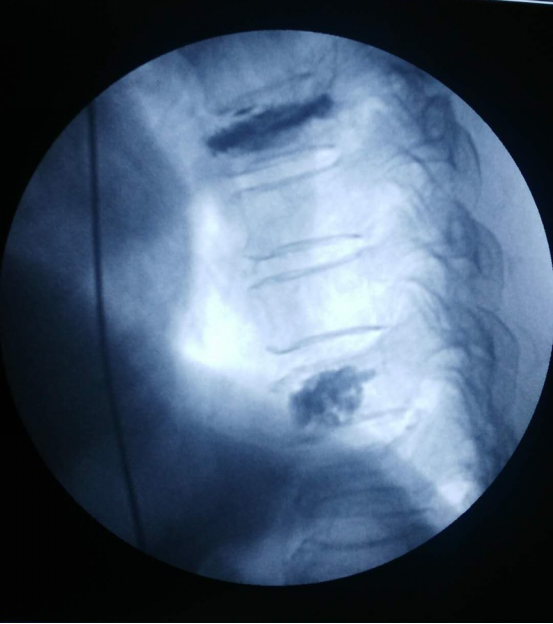

经过细致完备的术前准备,在局麻下为该患者实施了经皮穿刺椎体压缩骨折后凸成型术,在G型臂X光机透视定位目标T7、10椎体,用穿刺针在透视下穿刺入椎体,应用球囊缓慢撑开T7、10椎体,应用专用器械在监测下注入骨水泥T7约5ml,T10约3ml,透视见注入的骨水泥位置、形态良好,术毕,患者安返病房。患者随即感疼痛明显缓解,翻身自如。

术 后